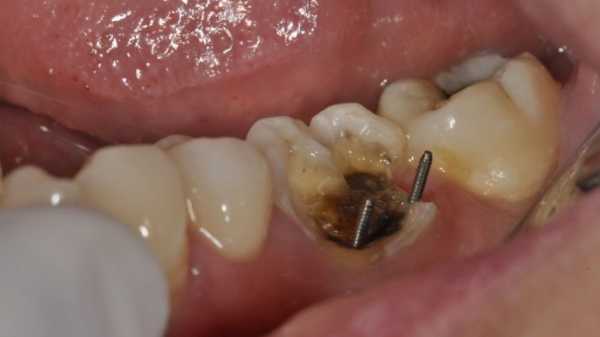

Установленный штифт

Фото: как ставят штифт в зуб